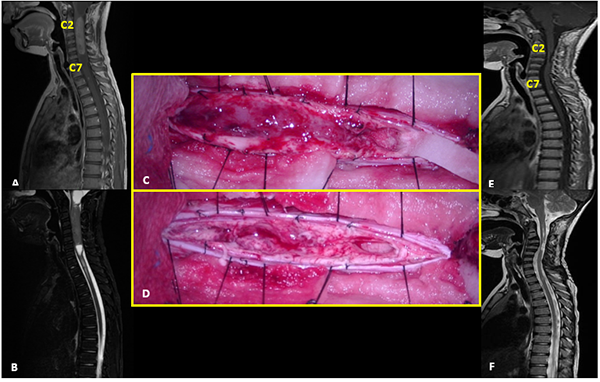

V: Ependimoma

Paciente sexo masculino con NF2 que comienza a los 7 años con cervicalgia de 2 meses de evolución refractaria a analgésicos evidenciando en la RM un tumor intramedular cervical (C2-C7) con realce post contraste y el “signo del gorro” típico de ependimoma. Se realizó exéresis completa de la lesión demostrado en la RM control. El monitoreo intraoperatorio mostró caída de la onda D cercana al 50%. El McCormick postoperatorio inmediato fue grado 3. A los 6 meses de seguimiento con rehabilitación se evidenció mejoría clínica con McCormick grado 1. La anatomía patológica informó ependimoma clásico. Posteriormente el paciente evolucionó con progresión de su enfermedad de base, con lesiones intracreneales que requirieron tratamiento quirúrgico y radiocirugía. Casi 6 años después de la resección del ependimoma cervical, presentó recidiva local (C3-C4) y aumento considerable de una lesión a nivel de C1-C2 intra-extradural que se controlaba con imágenes seriadas. Se realizó la exéresis completa de ambas lesiones en un mismo acto quirúrgico, cuya anatomía patológica reveló schwannoma para el tumor extramedular y ependimoma clásico con Ki67 de 6% para la lesión intramedular. Como complicación alejada presentó dehiscencia de la herida, que requirió cierre quirúrgico (Figura 5).

Figura 5:

Ependimoma. A-B: RM prequirúrgica T1 con contraste y T2 cortes sagitales. C-D: Imágenes intraoperatoria pre y postresección. E-F: RM postquirúrgica T1 con contraste y T2 cortes sagitales.